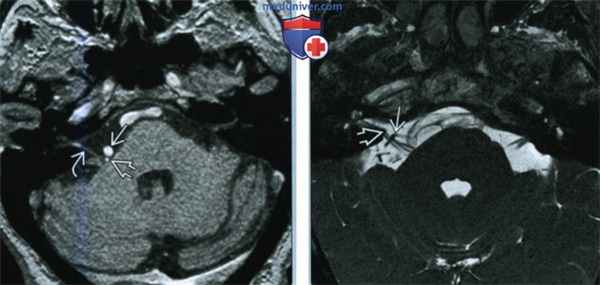

(Слева) При аксиальном исходном изображении (МРА) у пациента с спазмом правой половины лица визуализируются извитая правая позвоночная артерия и ЗНМА, воздействующие на область выхода корешка лицевого нерва. В цистерне мостомозжечкового угла (ММУ) визуализируется лицевой нерв.

(Справа) При аксиальной МРТ CISS на уровне цистерн ММУ у пациента с правосторонним гемифациальным спазмом определяется петля ЗНМА, смещающая ЧН VII в цистерне ММУ кзади, в результате чего он «свешивается» с заднего края слухового отверстия.